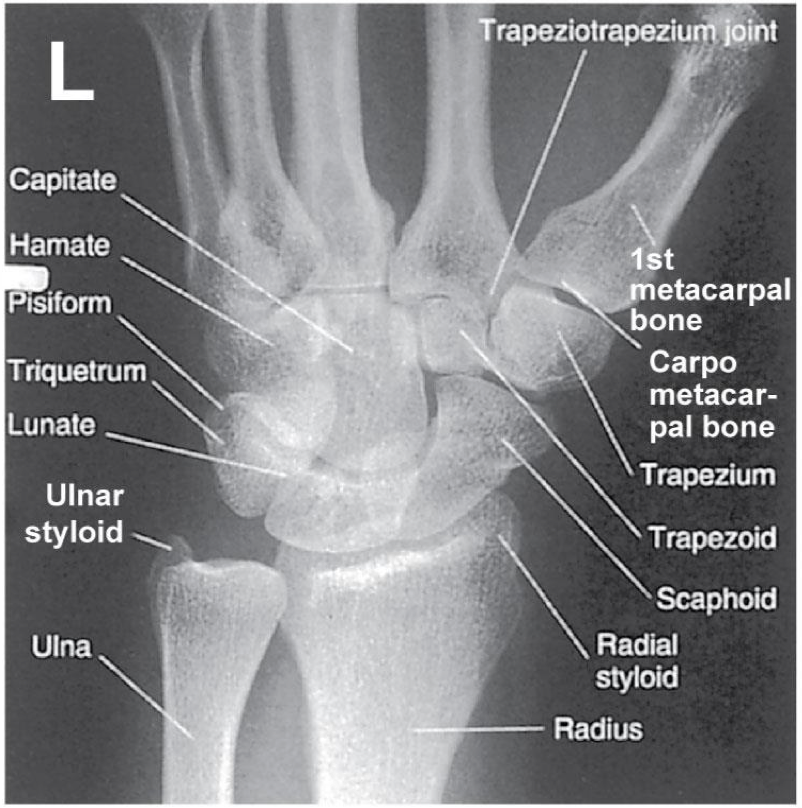

Evaluation Criteria for PA Wrist

• Distal radius/ ulna and carpals demonstrated

• Ulnar styloid process in profile

If humerus is not abducted & elbow flexed: the ulnar styloid process will not be in profile

• Open (or near open) radioulnar joint

• Center of field at midcarpals

• Long axis of 3rd metacarpal in line with long axis of forearm

• No rotation

• Exposure factors

Good soft tissue

Should demonstrate scaphoid fat stripe

scaphoid fat stripe

looks black, sign of fracture or dislocation. On PA and oblique wrist projections